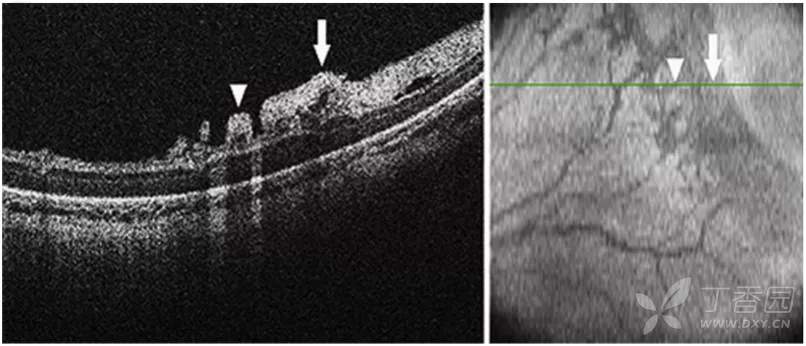

急性ROP4期OCT图像

图. 4A期视网膜脱离:OCT可见中心凹视网膜附着(星号),视网膜内渗出(高反射点)、周边部视网膜脱离和视网膜劈裂。

图. 4B期视网膜脱离:OCT可见中心凹视网膜脱离(星号),在检眼镜检查中很难识别。